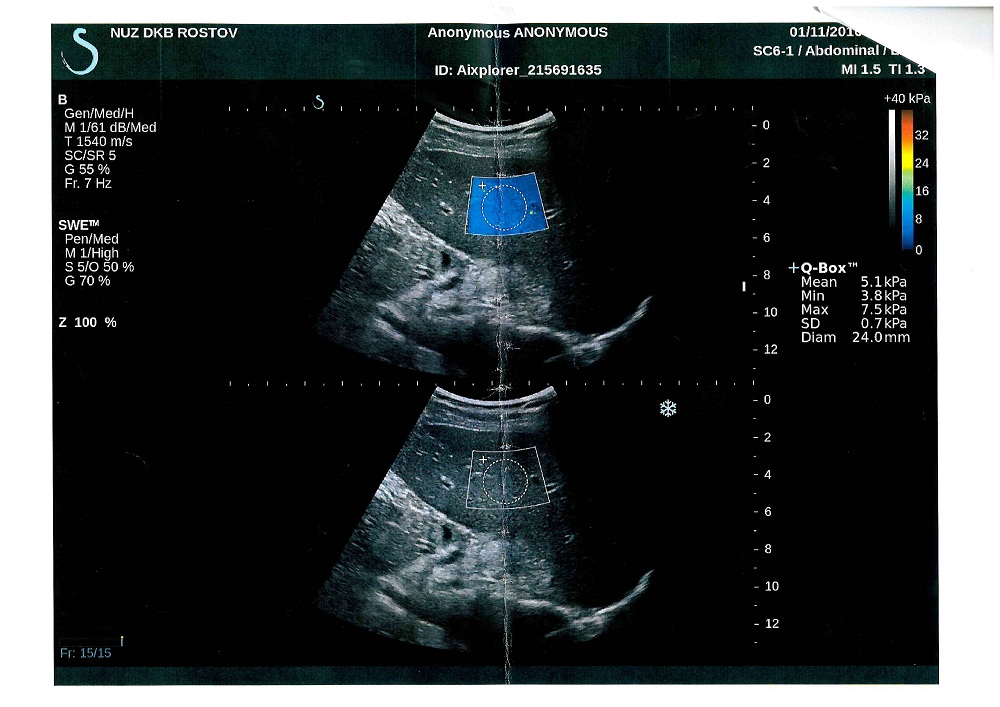

После поехал сдавать Фиброскан в клинику СКЖД - цена удовольствия - 1300р

результат фиброскана - F0-F1 - 5,1 КПА (что тоже радует бесспорно)